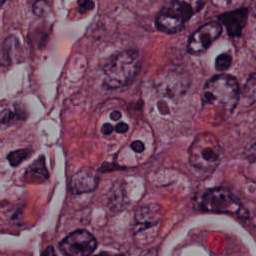

Blood Cell Artifact

Histopathology GMAIMMbench Cell Recognition

Blood Cell Artifact - L0 (Original)

L0

L0 (Original)

Blood Cell Artifact - L1 (Moderate)

L1

L1 (Moderate)

Blood Cell Artifact - L2 (Severe)

L2

L2 (Severe)

Question

Which cell type is indicated in the highlighted area of the Histopathology image?

A epithelial cell B cytoplasm C dead cell D photoreceptor cell

Ground Truth: C. dead cell